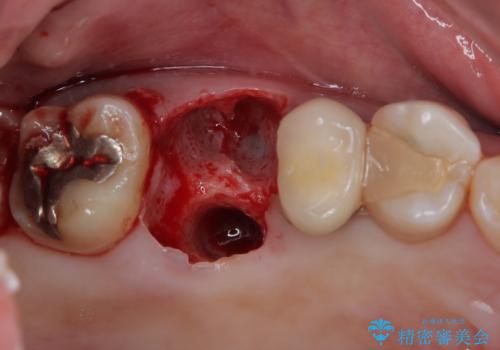

詰めている材料を外したところ、目視で確認できるほど割れており、要抜歯との説明をし、インプラント治療を行うこととしました。

骨量が十分にあることが3次元CTより確認されたため、事前に仮歯を用意した上で、抜歯即時埋入インプラントによる補綴治療を行うこととしました。

来院されるまではインプラント治療を躊躇されていましたが、抜歯即時埋入により、単回の外科処置で治療が終えられることのメリットを理解され、インプラントによる補綴治療を行いました。

スムーズに治療を終えることができました。